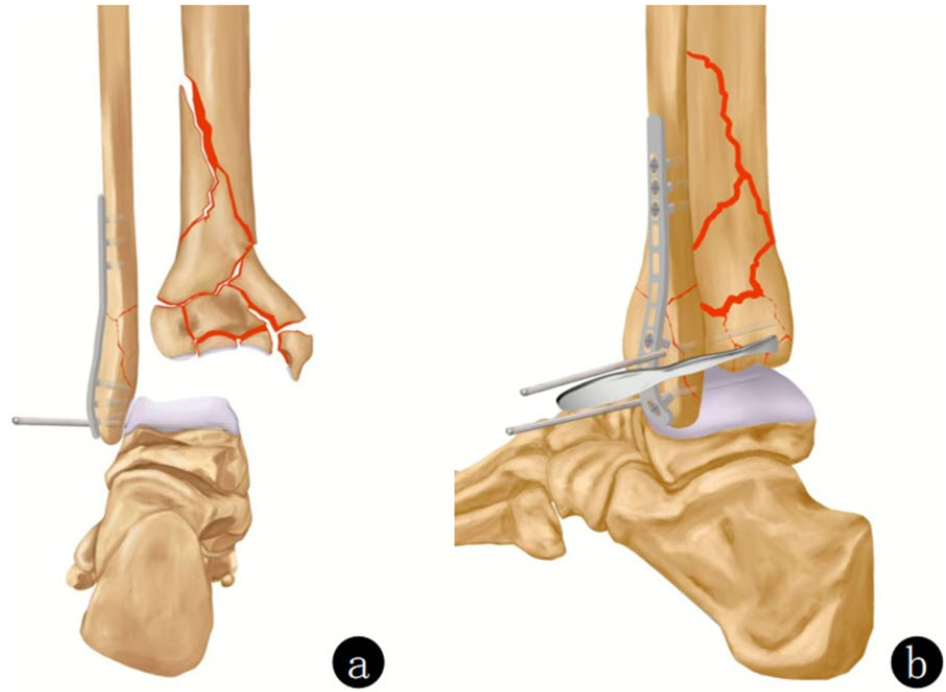

如果上述将C型骨折转化为B型骨折的策略无法实施,可以通过复位并临时固定关节块,将C型骨折转化为A型骨折。在复位关节面时,应以距骨为模板,按照从中心到周边的顺序进行操作。关节面复位完成后,再处理干骺端骨折。将解剖复位后的关节块临时固定,然后根据正确的力线、长度和旋转关系,将其与骨干进行对齐,并使用合适的内植物进行固定。这种方法特别适用于干骺端存在复杂粉碎区域,且关节骨块与干骺端/骨干之间缺乏明确骨性参照的情况。

图a、b. 术前X线片显示Pilon骨折(AO 43-C3)。由于干骺端存在粉碎区域,关节骨折块与完整的骨干之间缺乏参照;c、d. 通过 “扩大外侧入路” 联合小的内侧入路,首先对关节骨块进行解剖复位,从而将C型骨折转化为A型骨折。随后,对骨折进行功能对位并固定到骨干上。